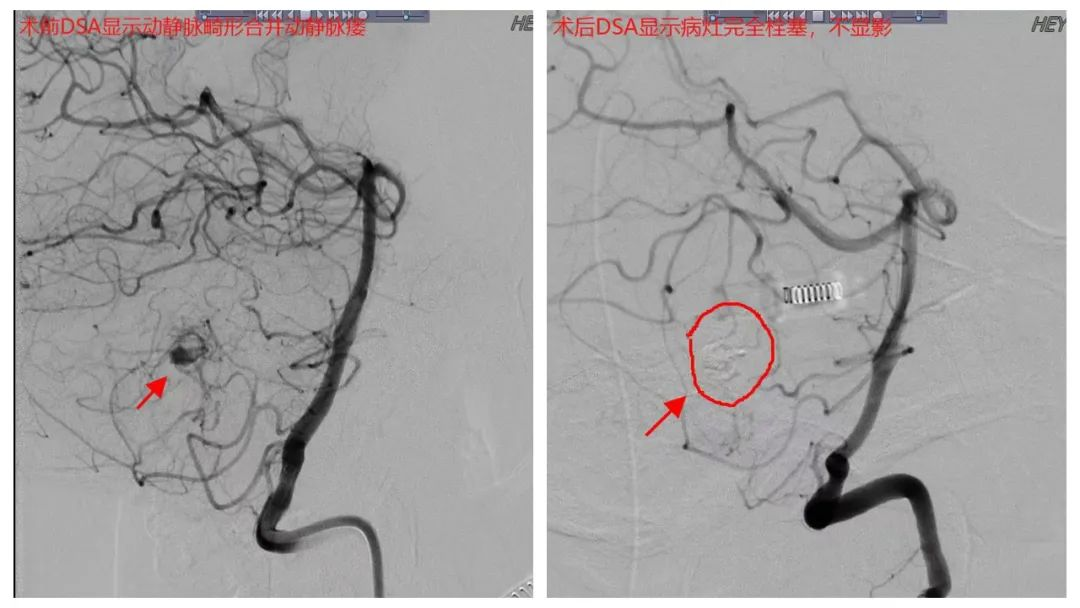

7月2日下午,经过充分术前准备、讨论,多学科会诊,陈光忠教授指导神经外科二区刘胜初主任医师团队为患者成功进行了小脑蚓部动静脉畸形(b-AVMs)合并动静脉瘘(AVF)血管内介入栓塞治疗,手术治疗时间仅20分钟,达到完全栓塞,没有发生并发症。

术前、术后DSA影像对比